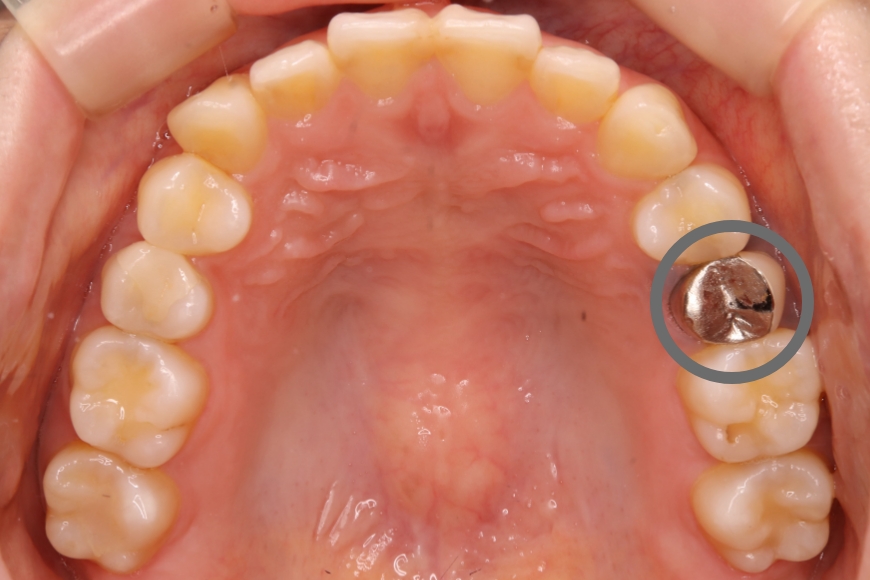

20代男性 上の前歯へのインプラント治療

治療内容 「前歯をきれいにしたい」との主訴で来院されました。

根っこが折れていたため抜歯後、「隣の歯は削りたくない」とのことでインプラント治療を希望されました。

インプラント予定部位の骨が少なく、歯ぐきも痩せていたので、GBR(骨造成)と結合組織移植(歯肉の移植)も施し、審美的な外観を整えました。

自然な感じの仕上がりとなり、患者様は、思いっきり笑うことができるようになりました。

治療期間・回数 治療期間:約10カ月

通院回数:10回程度

治療費用(総額)

560,000